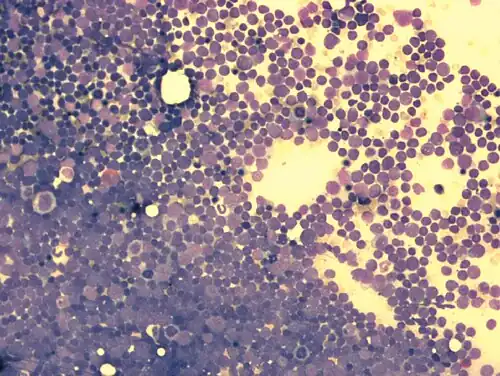

Zytomorphologie

Durch mikroskopische Untersuchung des Knochenmarks oder des Blutausstrichs bei leukämischem Verlauf kann die Diagnose einer akuten Leukämie gestellt werden. Für die weitere Subklassifikation der ALL spielt die Beurteilung der Zellmorphologie im Gegensatz zur AML nur eine untergeordnete Rolle. In der sogenannten FAB-Klassifikation („French-American-British“) wird zwischen drei verschiedenen Morphologien unterschieden (L1, L2, L3). Von Bedeutung ist das nur für den seltenen L3-Subtyp, der mit der „reifzelligen B-ALL“ assoziiert ist. Die reifzellige B-ALL ist eine Sonderform der ALL und kann als die leukämische Manifestation des Burkitt-Lymphoms betrachtet werden (d. h. ein Burkitt-Lymphom mit >20 % oder >25 % Knochenmarkbefall) und wird wie dieses behandelt. Die Unterscheidung zwischen L1 und L2-Morphologie ist dagegen schwierig und selbst sehr erfahrene Hämatologen oder Hämatopathologen kommen hier zu unterschiedlichen Einschätzungen. Klinisch hat die Unterscheidung von L1 und L2 keine Bedeutung.